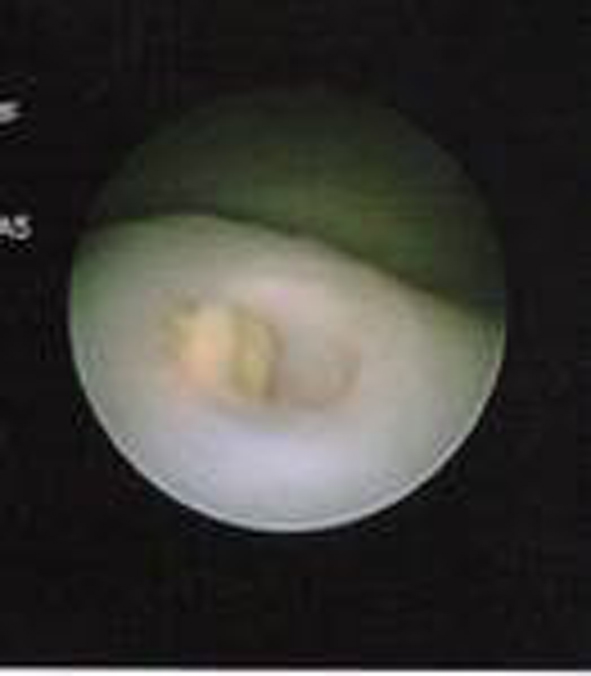

Wilms’ Tumor With Transureteric Extension Into Bladder